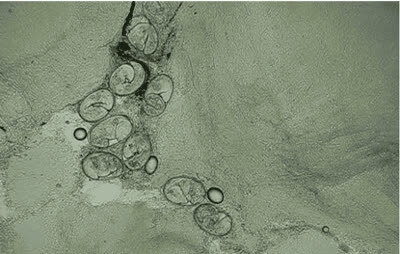

2. 这张动图显示的是嗜酸性粒细胞在趋化作用的“感知”下逐渐聚集到一只秀丽隐杆线虫周围并对它进行攻击的过程。有“成千上万”的嗜酸粒细胞围聚在线虫周围,就像一群蚂蚁,善打“包围战”。

3.这是中性粒细胞追击金黄色葡萄球菌的一个过程。免疫细胞捕捉细菌时是不是超萌!